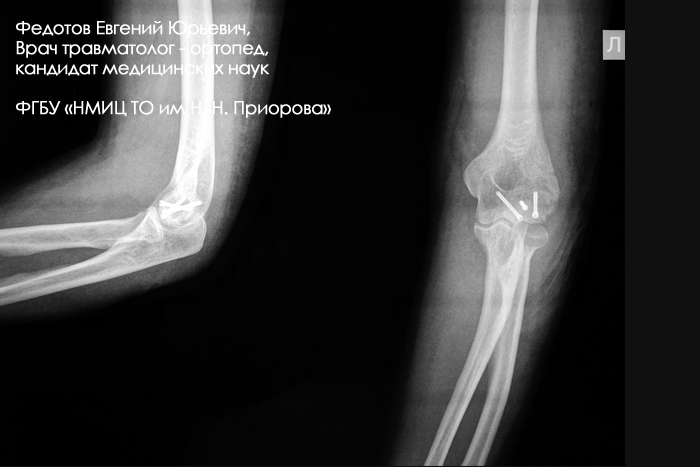

Закрытый внутрисуставной перелом головочки и части блока плечевой кости со смещением.

Операция: открытая репозиция отломков головочки и части блока плечевой кости, остеосинтез винтами.